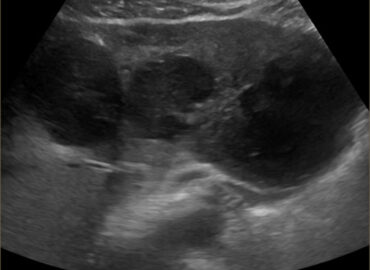

Femenina // 66 años MC: Dolor Abdominal AEA ● Dolor abdominal hipocondrio derecho y pérdida de peso EX FÍSICO […]